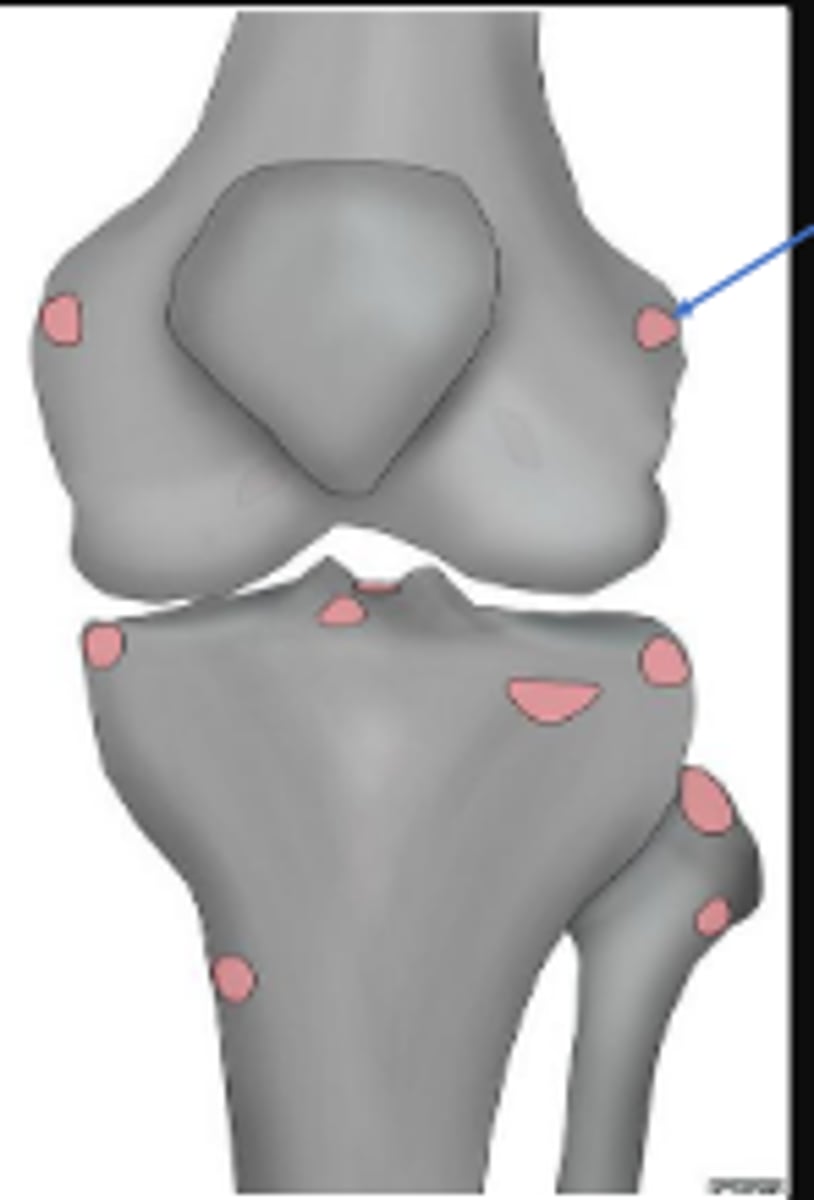

Lateral collateral ligament

What inserts at the location of the blue arrows?

Lateral collateral ligament avulsion fracture of

the right knee

What is the most significant radiographic finding?